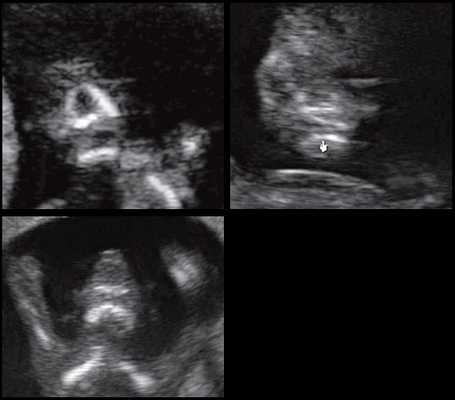

Революцией в пренатальной ультразвуковой диагностике явилось появление объемной эхографии, которая, обладая такими качествами, как неинвазивность, безопасность и возможность многократного применения у одной пациентки, имеет высокую информативность в исследовании анатомии плода и изучении его фенотипа. При применении различных режимов объемной эхографии абсолютно очевидно их преимущество по сравнению с обычным сканированием. Детально можно изучить лицо плода (рис. 1-4) в различные сроки беременности, начиная со сроков первого пренатального скрининга в 11-14 нед, конечности плода, причем не только их наличие и положение (рис. 5, 6), но и состояние и количество пальцев (рис. 7-9) как на руках, так и на ногах. Также можно изучить позвонки плода (рис. 10), состояние твердого нёба (рис. 11, 12), строение наружного уха (ушной раковины) (рис. 13), состояние основных швов черепа и родничков, исключая их преждевременное закрытие при кранисиностозах (рис. 14, 15).

С учетом особенностей зарастания швов формируется 2 типа краниосиностоза — сагиттальный (длинный узкий череп с выступающим лбом и большим затылком) и бикорональный (широкий короткий череп с деформированными лбом и глазницами). Тип краниосиностоза оказывает наибольшее влияние на особенности формирования неврологических расстройств.

Костные аномалии при болезни Карпентера формируются во внутриутробном периоде, поэтому они определяются сразу после рождения. Родители обращают внимание на вытянутую башнеобразную форму головы (акроцефалию). Со временем череп деформируется из-за раннего закрытия швов (краниосиностоза), которые ограничивают рост костей и не позволяют голове увеличиваться в объеме. Также наблюдаются множественные врожденные аномалии лицевого скелета.

Краниосиностоз проявляется разнообразными симптомами. При бикорональной деформации черепа отмечаются патологии зрительного аппарата: косоглазие, слезотечение, экзофтальм (выпячивание глазных яблок). Характерна задержка психомоторного развития: ребенок поздно начинает держать голову, плохо сидит и стоит, с трудом учится ходить. Также большое значение имеет косметический дефект, вызывающий у пациента при отсутствии коррекции психологическую травму.